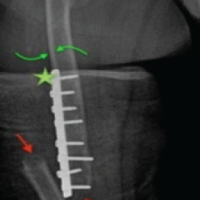

Surgery involved an open reduction of the medial malleolus through a medial ankle approach. The sagittal fracture line was stabilized temporarily with a Kirschner wire, and definitive fixation was achieved with two 2.5 mm headless cannulated compression screws (38 mm and 35 mm in length) (Fig. 1b). One-month post-op, the patient began physiotherapy, walking without complications, and ascending/descending stairs without issues. He reported only occasional pain, Visual Analog Scale 2/10 when walking on uneven surfaces. He returned to work as a fisherman 5 weeks after surgery. After completing physical therapy, follow-up was periodic. At his last check-up, 17-month post-op, he had no pain or complaints and exhibited normal function (neutral dorsiflexion and 60° plantar flexion).

Figure 1: (a): Pre-op anteroposterior (AP) and lateral X-rays of the left ankle showing multiple small (2–10 mm), well-defined, oval-shaped sclerotic lesions symmetrically distributed in the distal tibia, fibula, and talus, with no cortical disruption or periosteal reaction. A comminuted medial malleolus fracture is also visible. (b): Post-op AP and lateral X-rays showing the same sclerotic lesions and a fixed medial malleolus fracture with two cannulated screws.